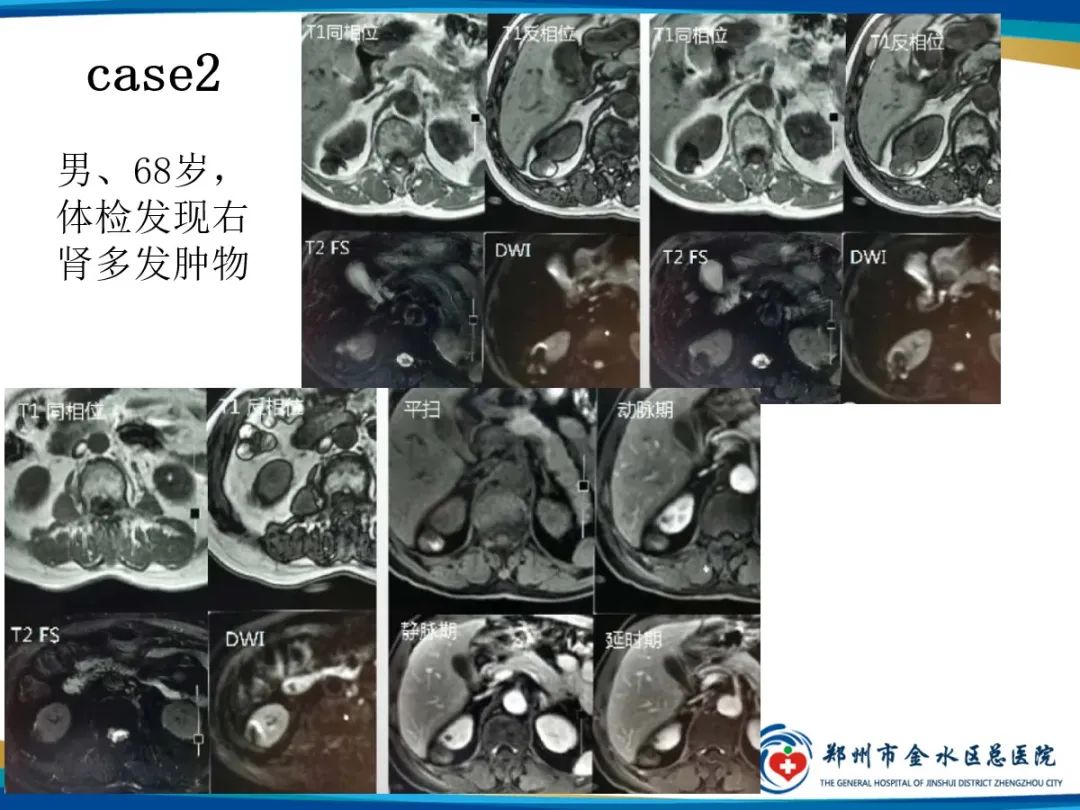

【PPT】肾细胞癌-2